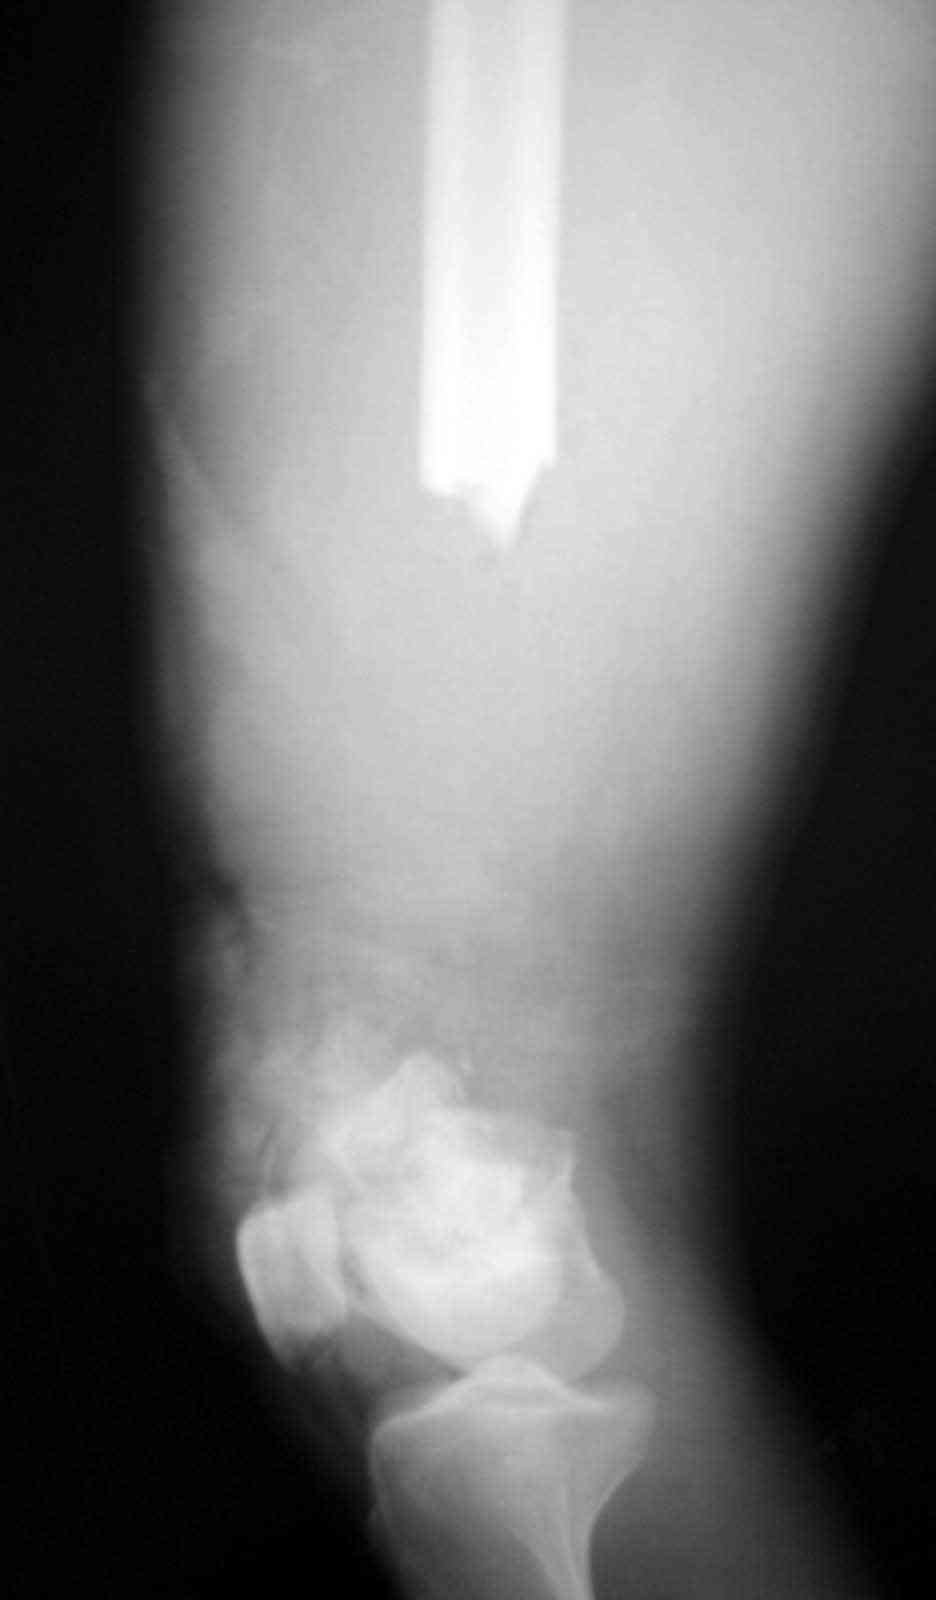

3 Diaphyseal endoprosthesis - see photo (dangerous in soft tissue loss and infection)

Similar case.

They do well with bone transport.

I do an acute or accelerated shortening to reduce the gap as much as proximal, and distract proximally to restore length.

In this particular case, notice the change of fixator - orthofix type of unilateral fixator worked well initially but did not allow me to compress beyond a point, which is when I changed to an ilizarov for further compression at the gap/nonunion site.